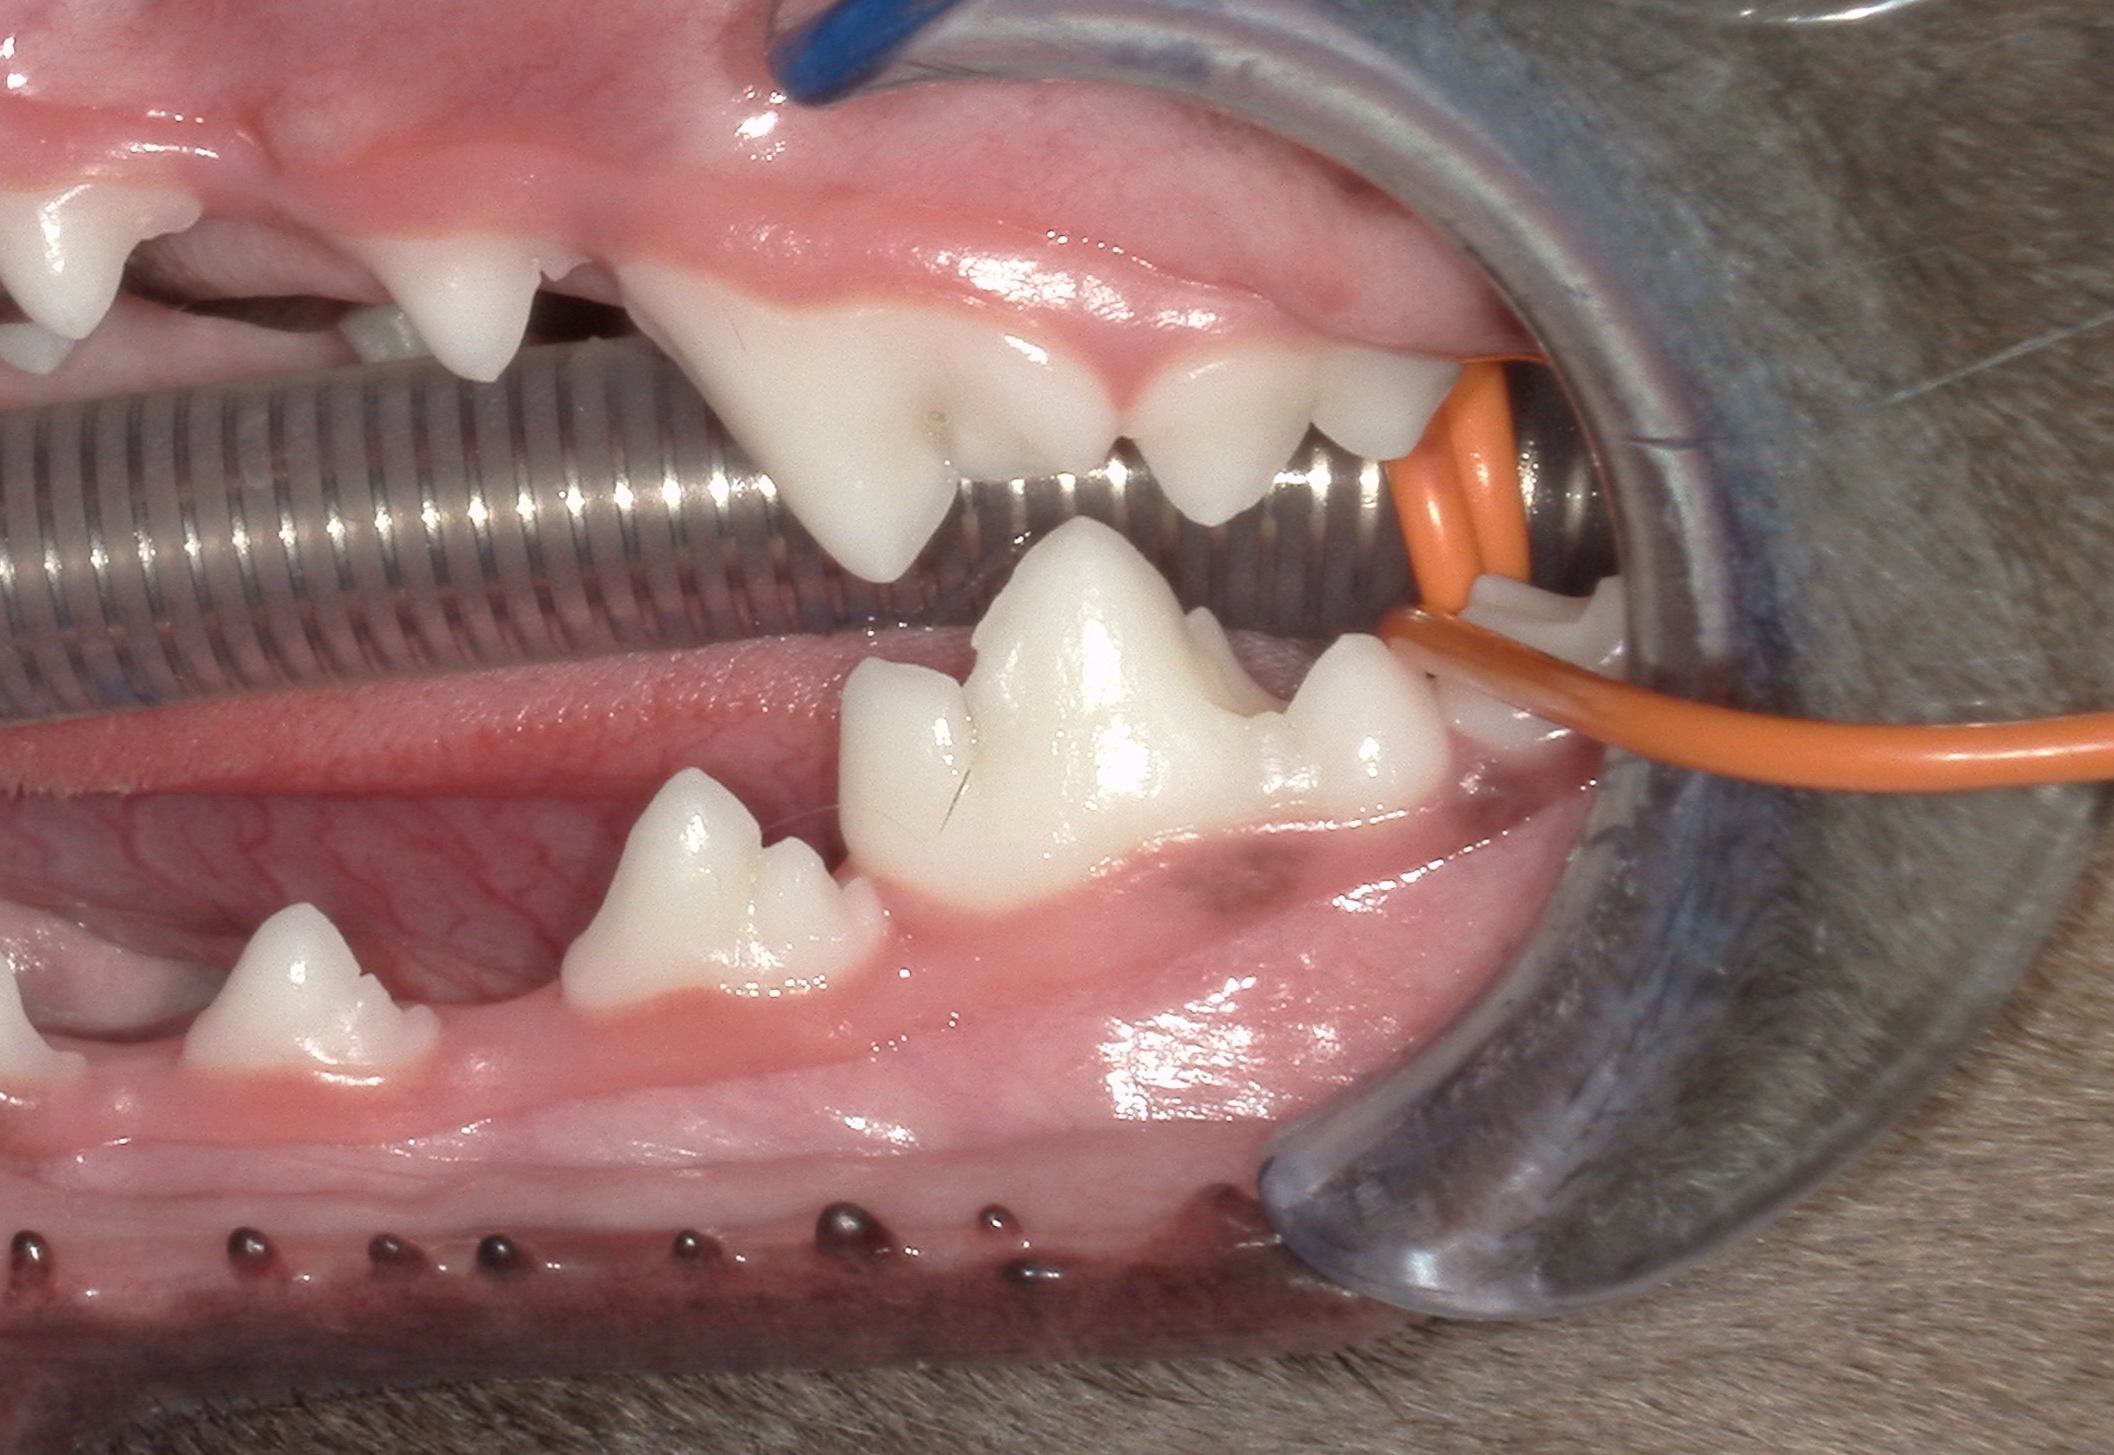

③ 麻酔下での歯科処置

全身麻酔をかけた後、口腔内を詳細に確認し、歯科用レントゲン撮影を行って精密な診断を行います。診断結果に基づき、歯石除去や抜歯など、それぞれの状態に適した治療を実施します。

-処置前-

-処置後-